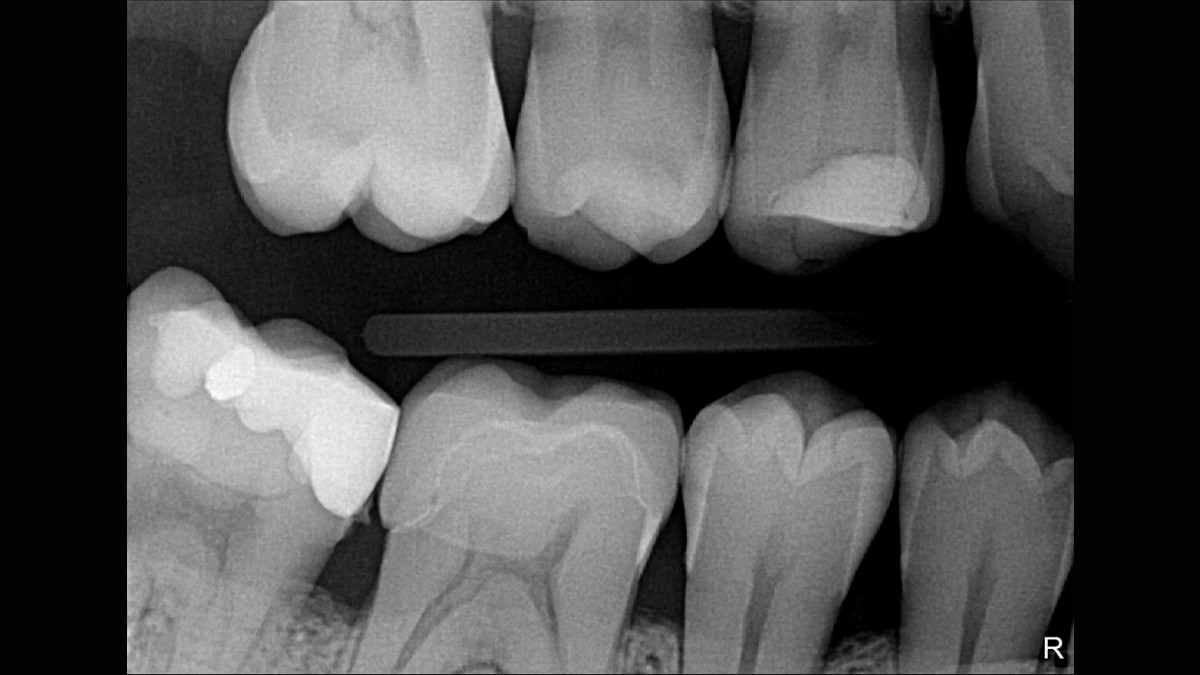

Excellent Image Quality

Xios XG Supreme provides a theoretical resolution of 33 lp/mm and a 15 μm pixel size.

Working with Xios XG Supreme: Filtering enhancements

With Xios XG Supreme sensors you have the option of five different filtering options: General Dentistry, Endodontics, Periodontics, Restorative and Hygiene. These clinically specific views are designed to optimize your diagnosis, enhancing the image to suit your needs.

Gallery of Sample Images